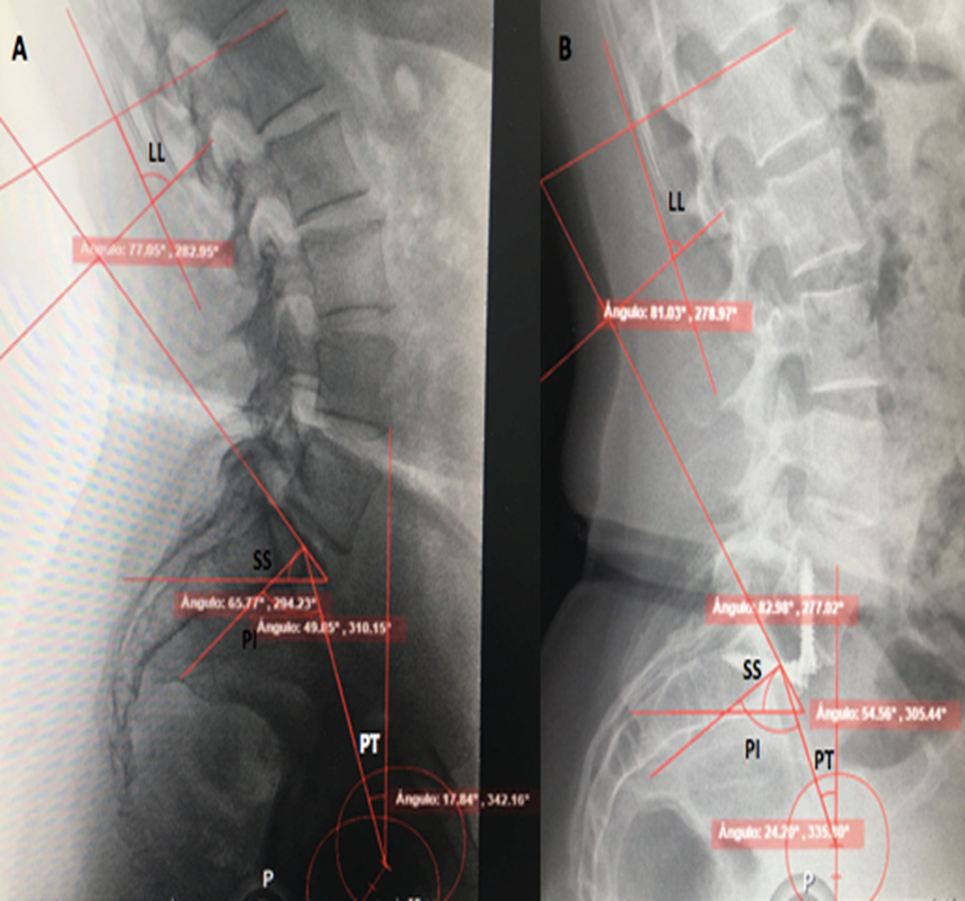

Spinopelvic Parameters in Anterior Lumbar Interbody Fusion, the First Follow-Up Study of Three Years in Mexican Population

Diego Quillo-Olvera, Javier Quillo-Olvera, Javier Quillo-Resendiz, Alfonso Vega-Sosa

International Journal of Innovative Research in Medical Science·June 27, 2019